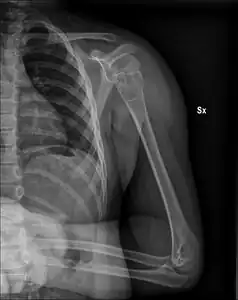

| X-ray: Simple bone cyst in left upper arm of 13 year old | |